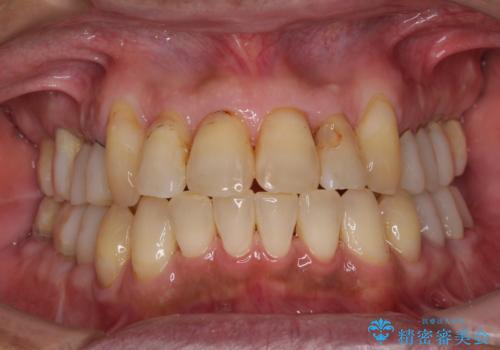

歯列不正と歯周病 総合歯科治療による全顎治療

- 前歯がのデコボコや、奥歯に咬んだときに痛みがあるとのことで来院された患者様です。

全体的に問題が多く、全てをしっかりと治療したいとのことでした。

全体的に中等度の歯周病と診断されたため、歯周外科処置やインプラントによる咬合回復から進めて行き、矯正治療による歯列改善を行った後にオールセラミッククラウンにて補綴することとしました。